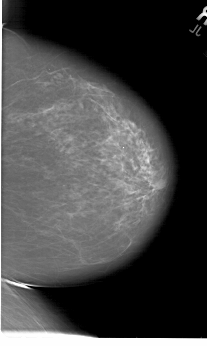

A_1821_1.RIGHT_MLO

RIGHT_MLO LINES 6871 PIXELS_PER_LINE 4276 BITS_PER_PIXEL 12 RESOLUTION 43.5 NON_OVERLAY